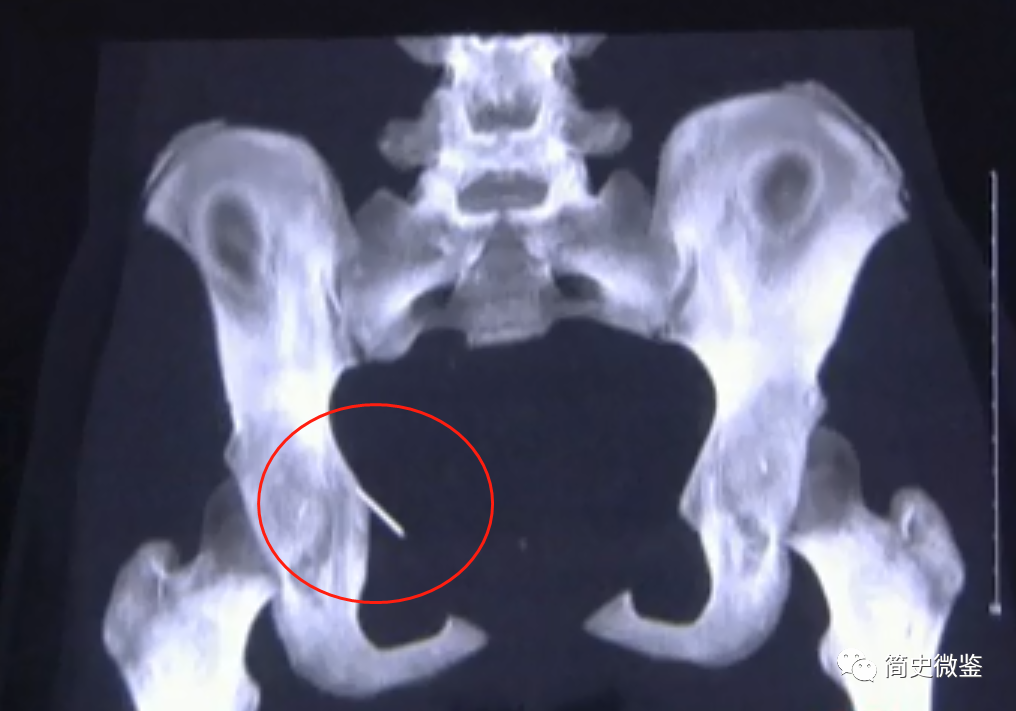

医生为小丽安排了细致的检查,但拿到CT的第一秒,所有人都震惊了!

“骨盆这里明显有一个亮点,应该是一个金属异物。”

仔细研讨后,医生分析,这是一颗长约两三厘米的尖锐断针,并且藏在骨盆内好几年了。

最重要的是,根据其所在位置,还能分析出断针一直跟着肌纤维的运动在游走。

结果看到螺纹CT后,医生全都倒吸了一口凉气,因为断针刚好就在直肠阴道和盆壁之间。

这是一个非常致命的位置,一旦断针划破直肠,或者刺穿子宫,都会引起大出血,影响今后的生育。

甚至严重的还可能导致不孕,威胁到生命安全。